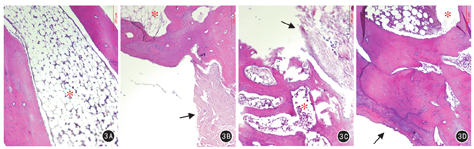

术后第12周组织学观察结果显示:A1组新生骨细胞排列规则,以成熟板状骨为主,髓腔再通(图3A);A2组缺损断端髓腔闭塞,有成熟板状骨向缺损中心生长,缺损区为部分纤维组织(图3B);B1、B2组断端主要为新生编织骨及少量成熟板状骨,骨细胞排列杂乱,缺损中央有较多纤维组织(图3C、图3D)。